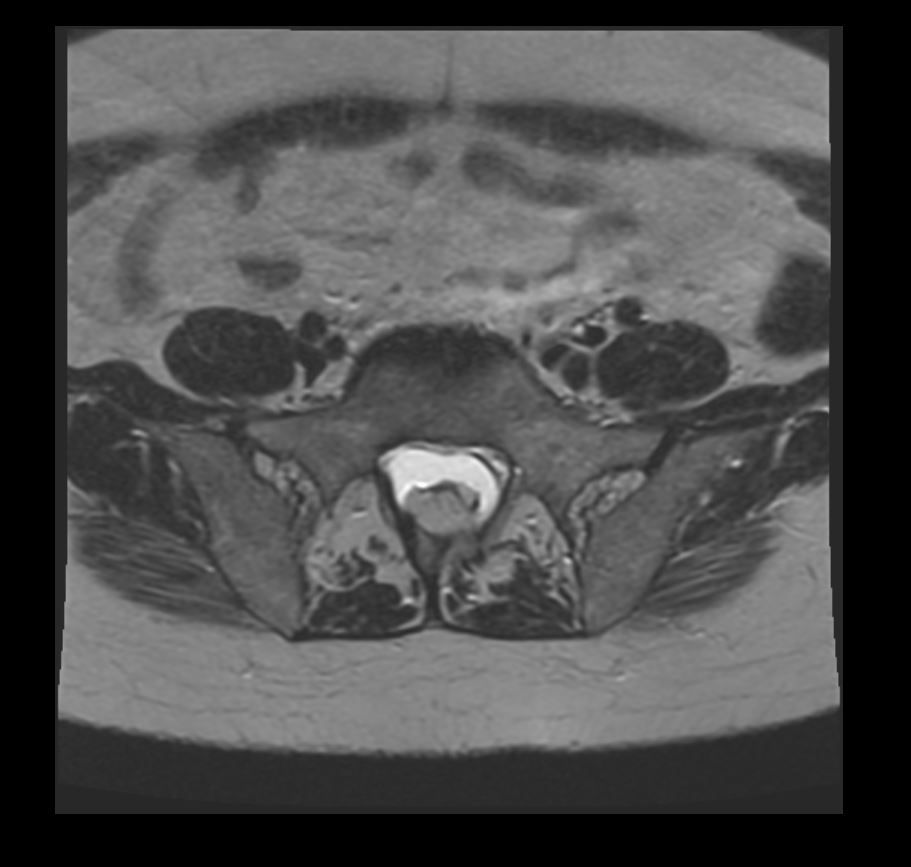

An elderly female presents with low back pain. What is the most likely imaging finding?